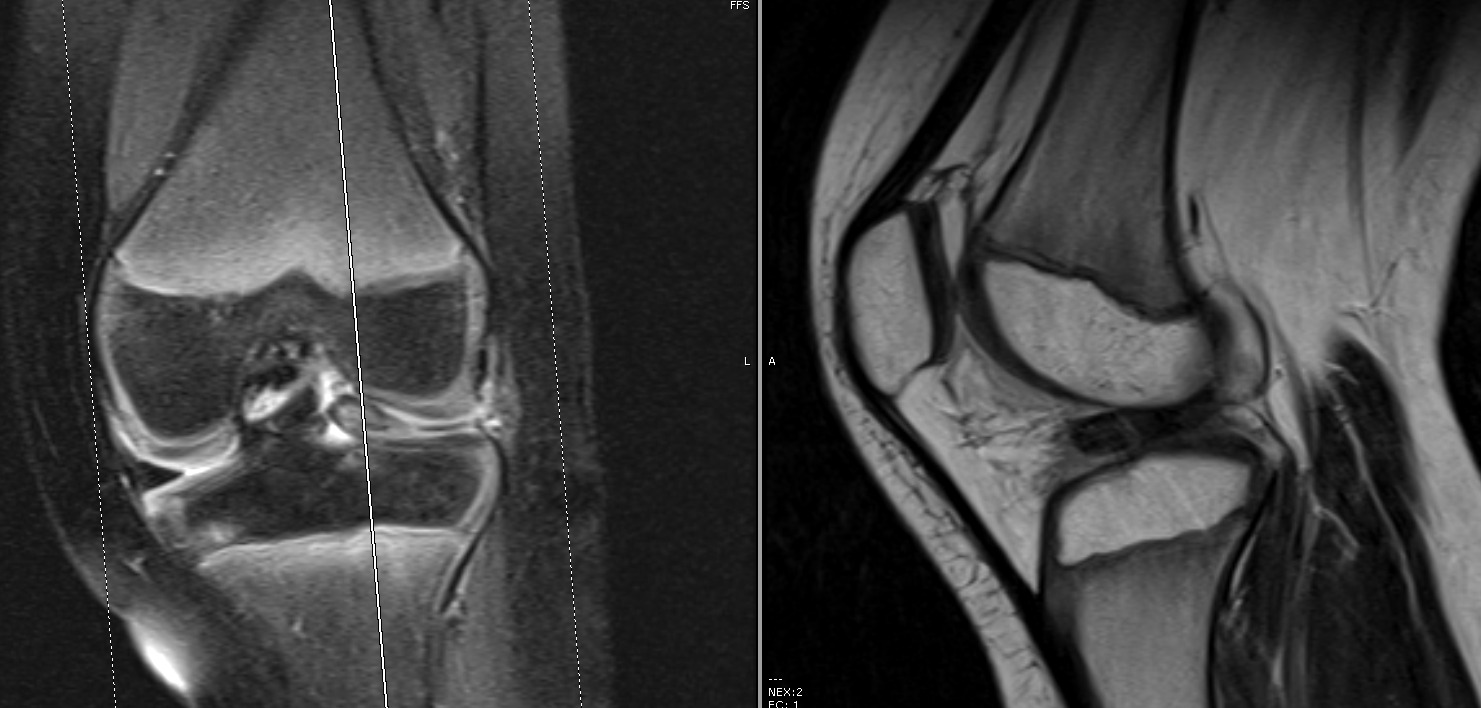

A MRI of the knee revealed a displaced tear of the anterior and posterior horns of the lateral meniscus (Figures 2 & 3).